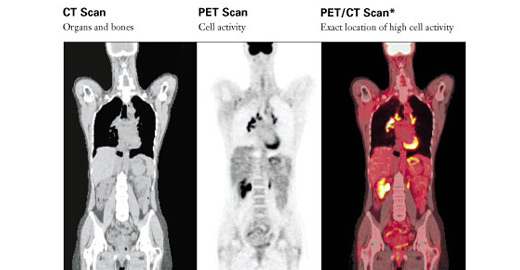

Cardiac Pet/ct

Enhance your business with our stunning commercial Cardiac Pet/ct collection of numerous professional images. optimized for commercial use with truck, vehicle, and automobile. ideal for corporate communications and branding. Discover high-resolution Cardiac Pet/ct images optimized for various applications. Suitable for various applications including web design, social media, personal projects, and digital content creation All Cardiac Pet/ct images are available in high resolution with professional-grade quality, optimized for both digital and print applications, and include comprehensive metadata for easy organization and usage. Discover the perfect Cardiac Pet/ct images to enhance your visual communication needs. Our Cardiac Pet/ct database continuously expands with fresh, relevant content from skilled photographers. Reliable customer support ensures smooth experience throughout the Cardiac Pet/ct selection process. Professional licensing options accommodate both commercial and educational usage requirements. Multiple resolution options ensure optimal performance across different platforms and applications. Regular updates keep the Cardiac Pet/ct collection current with contemporary trends and styles. Each image in our Cardiac Pet/ct gallery undergoes rigorous quality assessment before inclusion. Time-saving browsing features help users locate ideal Cardiac Pet/ct images quickly. The Cardiac Pet/ct archive serves professionals, educators, and creatives across diverse industries. Comprehensive tagging systems facilitate quick discovery of relevant Cardiac Pet/ct content.